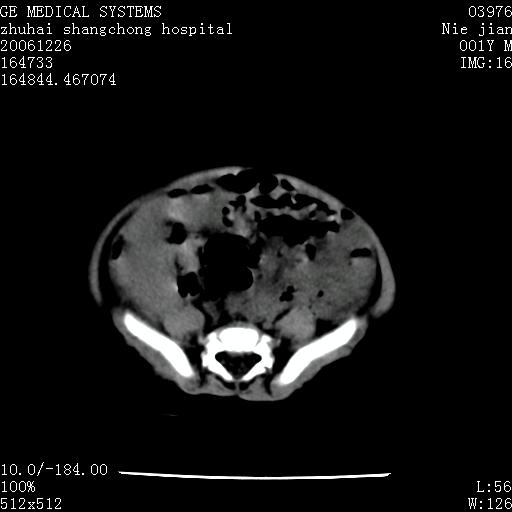

3个月婴儿腹胀来看。

【影像特征】

1、肝明显增大,肝弥漫性低密度灶。

2、肾上腺区见类圆形肿块,其内密度不均,见片状偏高密度。

1、肝弥漫性病变,考虑急性肝炎致广泛脂肪浸润可能性大。

2、肾上腺区占位,假性肿瘤?肾上腺血肿(感染所致)?

1、关键着眼点:肝脏弥漫性病变内有没有走形的血管,仔细看部分低密度内有血管影(要有增强扫描作为证据就好了),说明并非肿瘤样病变,而是脂肪浸润。即可能不是转移瘤或原发肿瘤,低密度的形态上看,是片状,也不像肿瘤。

4、肾上腺出血也可见于败血症及感染,通常包块在数周内消失,ct表现包块内有偏高密度,可能是亚急性血肿的表现。假性肿瘤即腹部肠管积液、扩张血管及邻近结构的伪像。自然会消失。

5、因此,感染可以贯穿一切,解释一切。肿瘤自然消退?可能吗?那些应要无道理的创造奇迹的事情会那么容易发生吗?

楼主反馈的结果:该患儿曾在大医院看了,也劝其放弃治疗,不得已抱回家等,据说这一年中曾得过一次肺炎,做过治疗,再没别的治疗。反正一年多了还活得好好的。